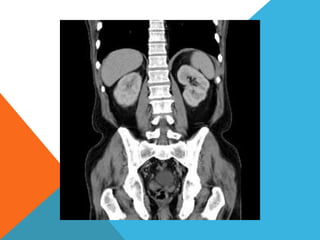

El paciente presentó síntomas de sangrado digestivo y pérdida de peso. Exámenes revelaron gastritis crónica asociada a H. pylori. Un tumor fue descubierto en una colonoscopia normal. La cirugía removió un tumor fibroide solitario, una rara neoplasia mesenquimal que usualmente crece lento y tiene bajo potencial de malignidad. El pronóstico después de la remoción quirúrgica es generalmente bueno.